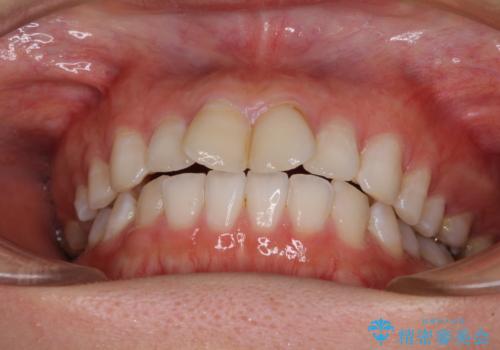

前歯の捻れを改善 インビザラインによる矯正治療

- 前歯の翼状捻転を気にして来院された患者様です。

全体的に叢生は軽度であったため、インビザラインにて矯正治療を行うこととしました。

前歯の幅の大きさも気になっていたため、IPRにより叢生を解消するとともに、歯の大きさも改善しました。